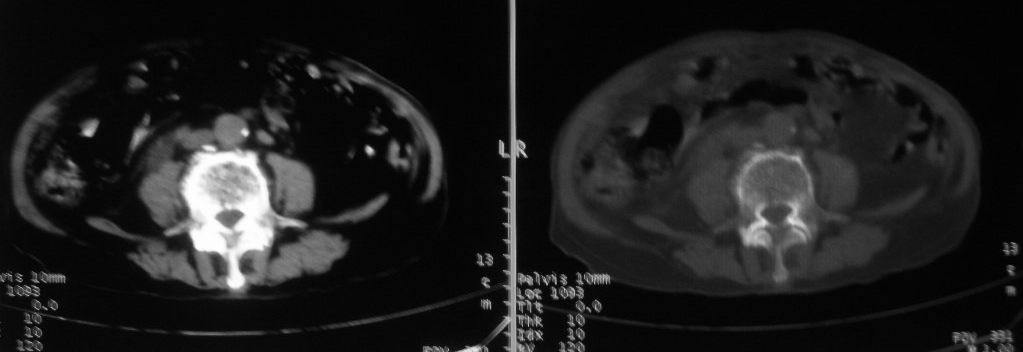

以下是引用zjzjr在2008-10-3 12:59:00的发言:[br]前列腺癌伴左髂骨\\腰椎转移可能性大.

以下是引用卜一在2008-10-3 13:40:00的发言:[br]前列腺癌!左髂骨\\腰椎转移?建议行全身骨扫描!

以下是引用深泽交通医院在2008-10-3 15:33:00的发言:[br]前列腺实性增大伴分叶状,与包膜间隙境界不清;椎体松质区间结节样密度影,考虑:前列腺癌,并椎体成骨性转移